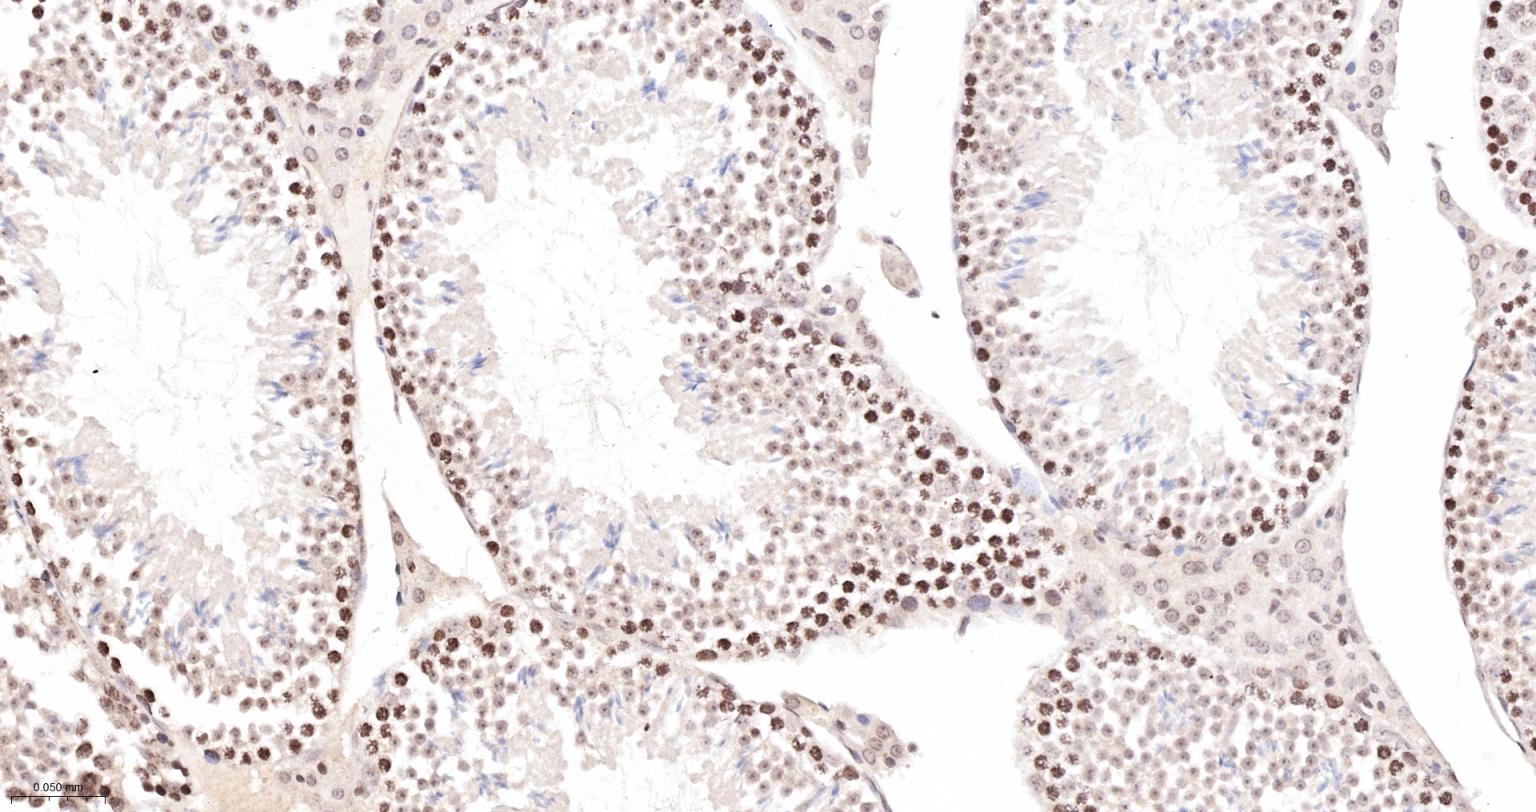

Paraformaldehyde-fixed, paraffin embedded Mouse Testicles; Antigen retrieval by boiling in sodium citrate buffer (pH6.0) for 15 min; The section was incubated with Survivin Monoclonal Antibody, Unconjugated (bsm-54474R) at 1:200 overnight at 4°C, followed by conjugation to the bs-0295G-HRP and DAB (C-0010) staining.